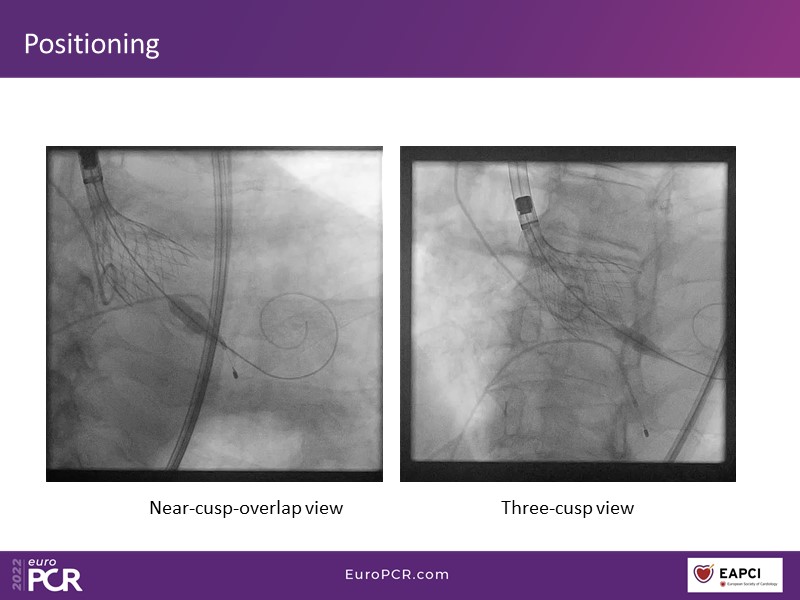

Your most challenging TAVI cases - Achieving precision and control with Evolut platform

How to deal with challenging anatomies? Find answers in this EuroPCR 2022 session with case studies to explore and learn how to achieve optimal patient outcomes with Evolut platform, uncover practical tips and techniques to achieve implant precision and control, and become familiar with technical considerations and procedural execution of TAVI.

- To uncover practical tips and techniques to achieve implant precision and control